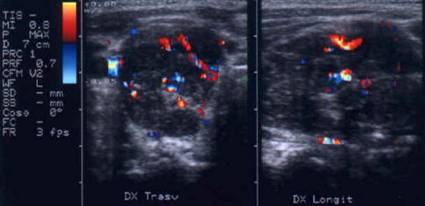

Femeie de 36 ani. Cunoscuta cu maladie Graves. La un

an dupa prima tiroidectomie totala pentru neoplazie papilara multifocala cu

metastaze in ganglioni (pT4b N1 M0).

Mica formatiune nodulara medial de carotida dreapta (0,2 cc), marcat

hipoecogena.

Tireoglobulina: < 2 ng.

Examen citologic: carcinom papilar.

Aceeasi pacienta - hipervascularizatie interna la doppler color si powerdoppler